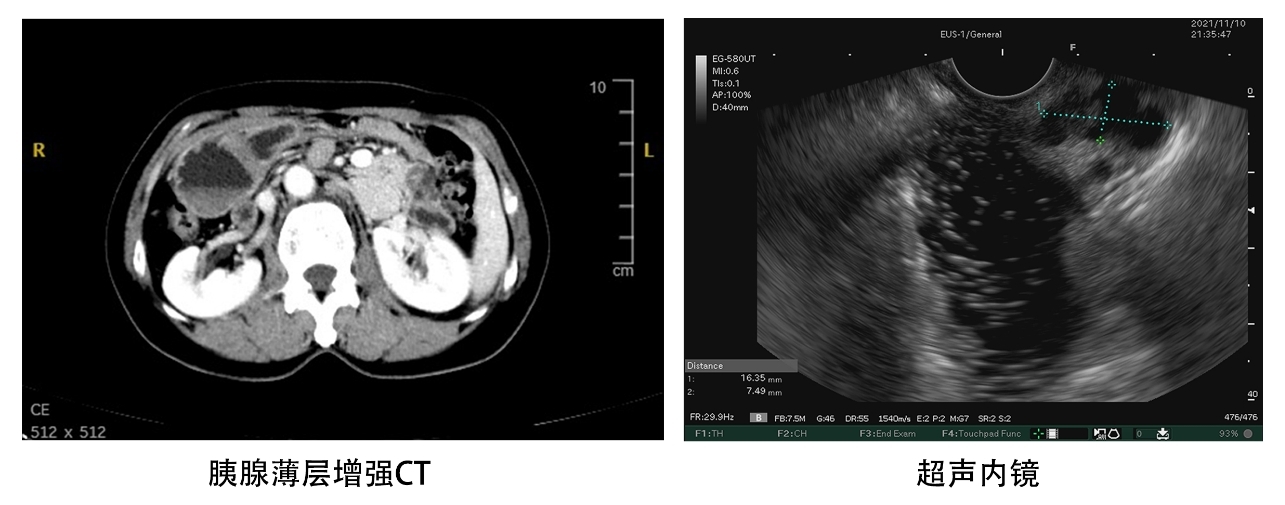

在对患者影像学资料充分分析并加做超声内镜检查后,刘亮教授认为患者胰头部肿瘤为胰腺导管内乳头状粘液性肿瘤(IPMN),由于其中存在明显壁结节,引起胰管狭窄和胰液粘稠排泄不畅,可能是导致患者胰腺炎反复发作的首要原因。 “镜面人”的生理解剖与普通人相差甚大,手术的复杂程度和难度系数也随之加大,但由于IPMN胰腺癌癌前病变出现壁结节后癌变几率更是加大。因此,刘亮教授将此特殊病例提交以楼文晖教授领衔的中山胰腺肿瘤MDT进行多学科讨论,各位专家形成统一意见:对该患者实施胰十二指肠切除术是可行的、安全的、必要的!